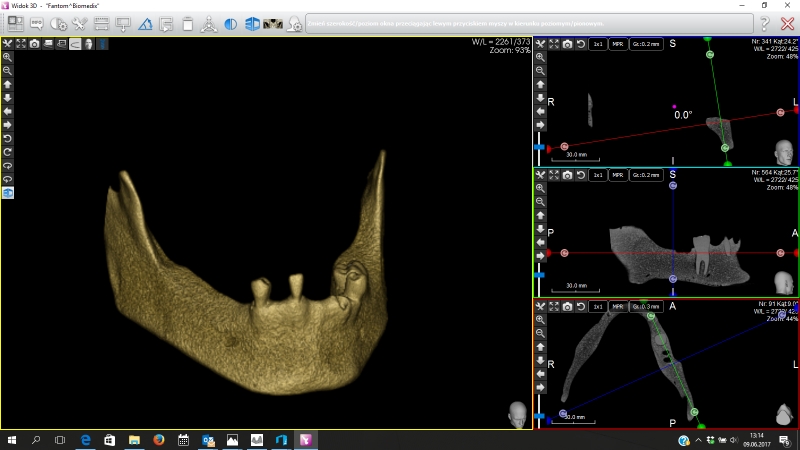

Żuchwa do fantomów z wyrostkiem zębodołowym wyścielonym imitacją błony śluzowej oraz zębami 10-3040

• Żuchwa do fantomów z wyrostkiem zębodołowym wyścielonym imitacją błony śluzowej oraz zębami 10-3040

Żuchwa do fantomów z wyrostkiem zębodołowym wyścielonym imitacją błony śluzowej oraz zębami wraz z ich korzeniami  w pozycji 37, 33, 43 oraz z niezagojonym zębodołem w pozycji 42. W modelu odwzorowano kanały żuchwy i otwory bródkowe. Płytka mocująca umożliwia montaż do większości fantomów znajdujących się na rynku. Model ten można zamontować w dowolnym artykulatorze lub fantomie dentystycznym popularnym na rynku (zalecany manekin to 11-1000).

Poniżej znajduje się przycisk umożliwiający ściągnięcie pliku STL przeznaczonego do wykonanie szablonu do szkoleń implantacyjnych z użyciem modelu.

Numer katalogowy 10-3040